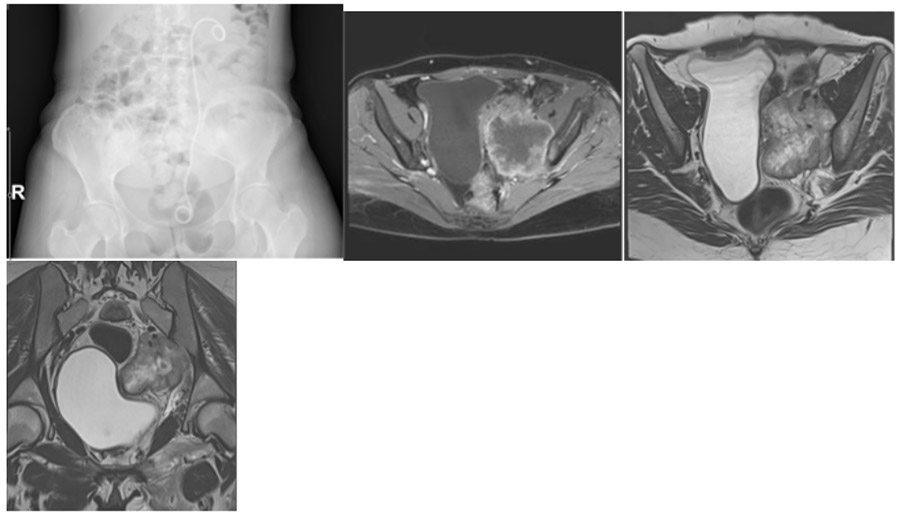

CASE 13: Cervical cancer metastasis to the left pelvic bone (sacroiliac joint)

Before surgery: X-ray shows no significant image in the left ureter except for a catheter, while MRI reveals a large soft tissue mass at the level of the left sacroiliac joint with irregular borders, a gas shadow, and displacing the bladder.